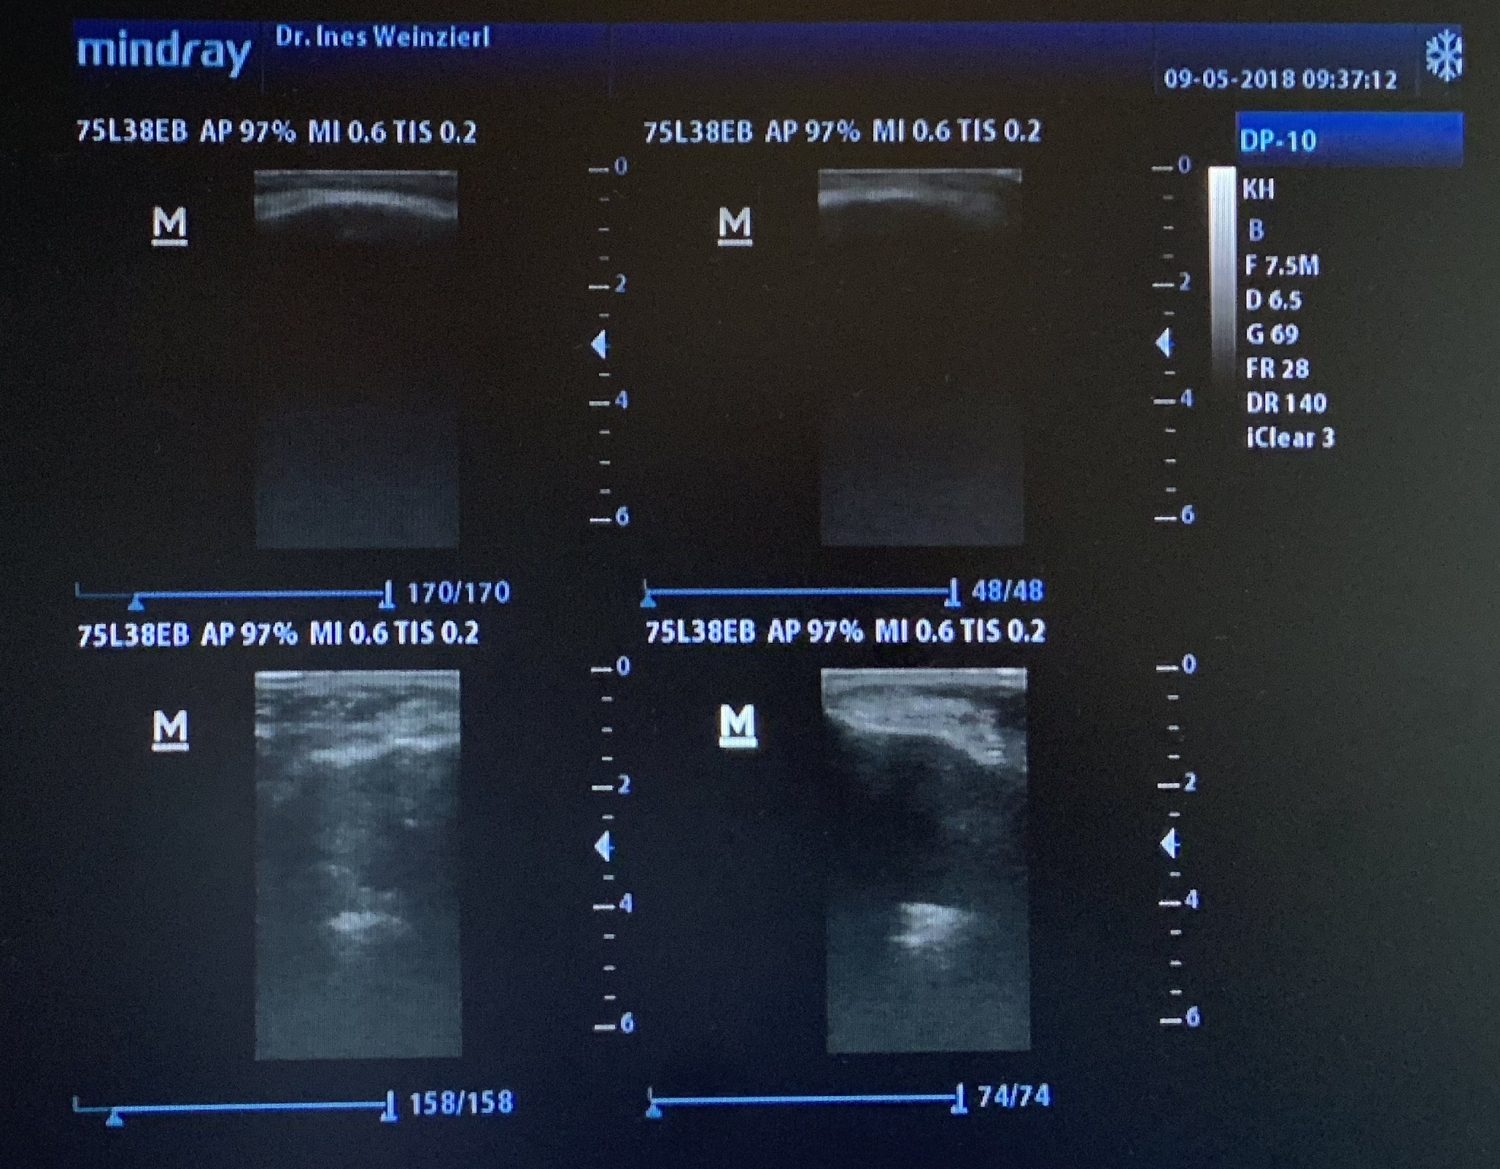

Source: kudoshubyfn.pages.dev Schleim im Hals HNOPraxis Dr. Weinzierl Nürnberg , Häufig sin die Beschwerden durch Reflux oder auch eine chronische Nasenenbenhöhlenentzündung ausgelöst. Seit Monaten plagte mich ein chronischer Schleim im Hals, der mich oft am Tag und sogar nachts weckte